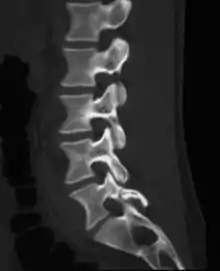

Spondylolyse

La spondylolyse est une perte de continuité de l'isthme articulaire (pars interarticularis), situé entre les deux apophyses articulaires supérieure et inférieure de l'arc vertébral postérieur. Elle survient le plus souvent au niveau d'un étage vertébral lombaire bas, habituellement le dernier étage mobile. Elle peut être unilatérale ou bilatérale, induisant alors une micro mobilité ou une mobilité de l'arc postérieur. Elle peut être aigüe, traumatique, correspondant à un trait de fracture vrai, ou chronique, sans notion de vrai traumatisme. La perte de continuité s'organise alors sous la forme d'un tissu fibreux ou plus rarement pseudo kystique plus ou moins hypertrophique dit « nodule de Gill », qui peut être agressif pour les racines nerveuses au contact. La lyse peut survenir dans l’enfance, mais aussi à l’âge adulte.